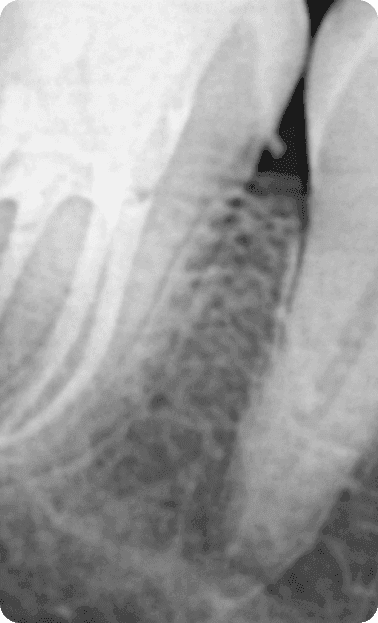

A Endocardite Bacteriana é uma infecção bucal, por isso, a causa mais comum é a falta de higiene adequada na cavidade oral. Quando a cárie penetra no canal, as bactérias podem cair na corrente sanguínea e serem levadas até o coração. Por isso o tratamento de canal deve ser corretamente executado e acompanhado para não gerar uma infecção generalizada.

Além disso , foi pioneiro no uso de Microscopia no tratamento de canal em nosso estado , aprimorando a qualidade , rapidez e segurança de seus tratamentos.